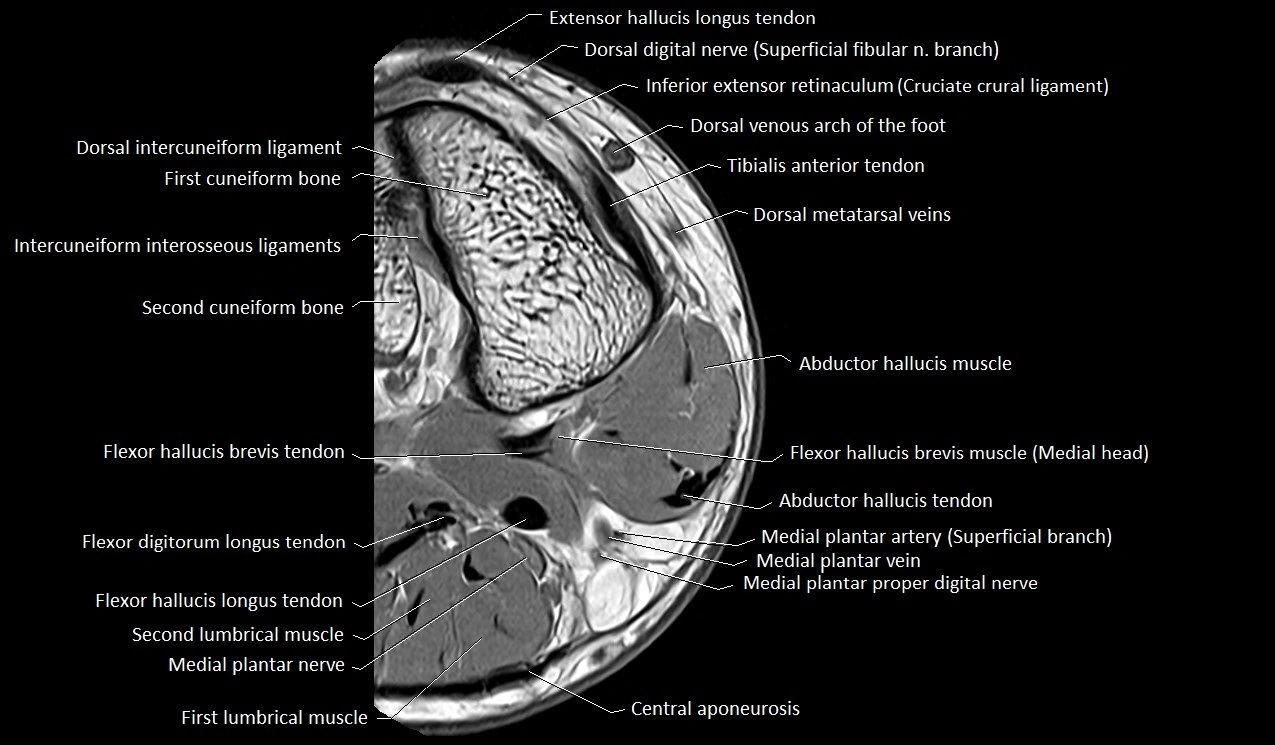

MRI image

image